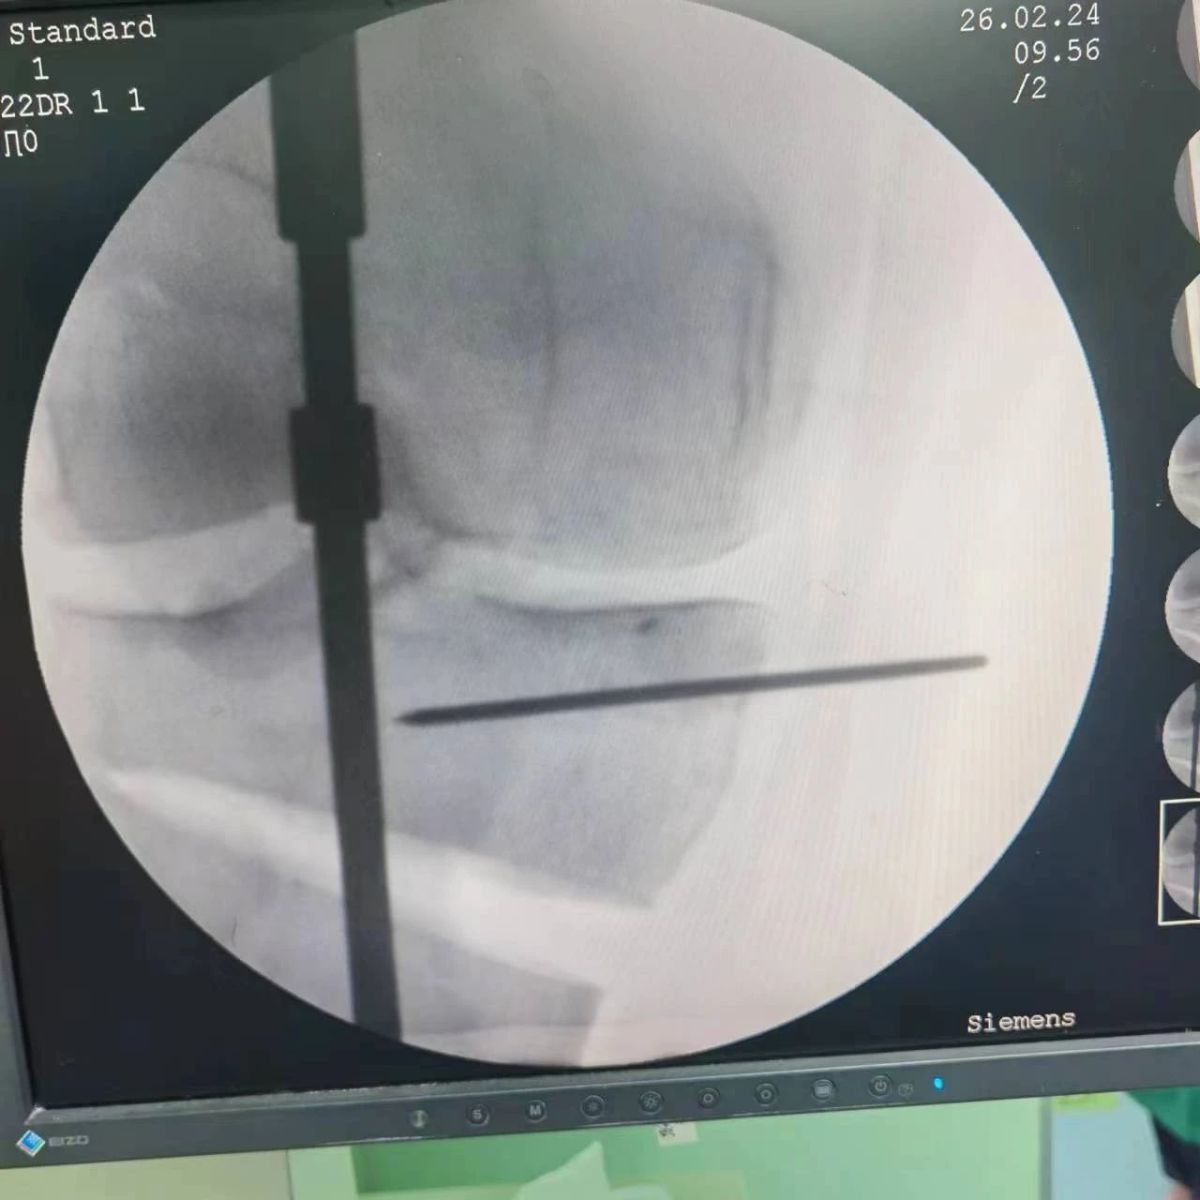

2月26日,漯河市骨科醫(yī)院(漯河醫(yī)專二附院、漯河市立醫(yī)院)膝關(guān)節(jié)外科、運(yùn)動(dòng)損傷科(骨六科)在保膝治療方面取得了新的突破,李付彬主任帶領(lǐng)岳龍等團(tuán)隊(duì)醫(yī)師,順利完成“計(jì)算機(jī)精準(zhǔn)術(shù)前規(guī)劃聯(lián)合3D打印截骨導(dǎo)板輔助脛骨高位截骨治療膝關(guān)節(jié)骨性關(guān)節(jié)炎”的手術(shù),這在漯河市尚屬首例!

李付彬主任團(tuán)隊(duì)通過(guò)精準(zhǔn)術(shù)前規(guī)劃,設(shè)計(jì)目標(biāo)力線及調(diào)整撐開(kāi)角度,轉(zhuǎn)化成需要撐開(kāi)的高度,最終設(shè)計(jì)出同等高度的填充塊,術(shù)中驗(yàn)證力線調(diào)整與術(shù)前規(guī)劃完全一致!

鋼板位置、螺釘位置及長(zhǎng)度均可通過(guò)術(shù)前規(guī)劃計(jì)算,術(shù)中通過(guò)定位操作,基本與術(shù)前規(guī)劃一致,手術(shù)快速高效完成,外側(cè)合頁(yè)保留完整。無(wú)任何并發(fā)癥出現(xiàn)。術(shù)后見(jiàn)鋼板位置及力線糾正近乎完美!

OWHTO手術(shù)效果依賴于多個(gè)數(shù)據(jù)參數(shù),比如:截骨的入點(diǎn)、合頁(yè)位置的選擇、截骨線的深度、截骨線的方向、撐開(kāi)的距離等,依托計(jì)算機(jī)術(shù)前精準(zhǔn)規(guī)劃和3D打印導(dǎo)板可輔助醫(yī)生精準(zhǔn)控制上述參數(shù),使截骨更準(zhǔn)確,真正達(dá)到精確的力線調(diào)整,減少術(shù)中透視次數(shù),縮短手術(shù)時(shí)間并降低手術(shù)風(fēng)險(xiǎn),從而使得OWHTO得到更好的應(yīng)用,造?;颊?。